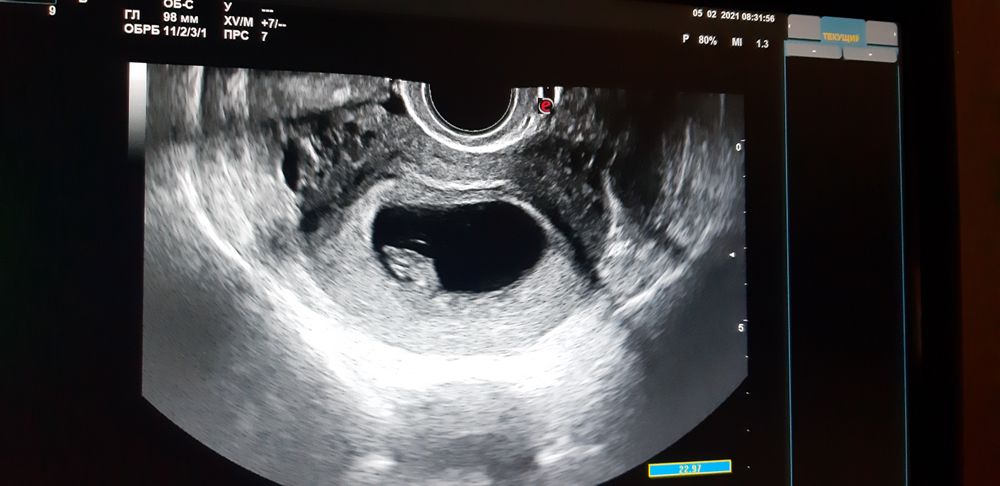

Новогодние праздники, муж знает о задержке, просит сделать тест, отправляет в ванную, а я сопротивляюсь, говорю ну подумаешь 3 дня задержки,бывает сбой,а он настаивает и просит сделать, уговорил, пошла в ванную, делаю все медленно не торопясь , боясь увидеть отрицательный тест... и тут на моих глазах появляется первая, а затем вторая полоска... она слабая очень , но видна на глаз. Выбегаю с ванны, говорю мужу ты станешь папой! Руки дрожат, на глазах наворачиваются слезы от счастья, он улыбается с широкими выпученными глазами и спрашивает в недоумении: ЧТО??? ЧТО??? Покажи !!!??? Положительный??? Счастливый радуется, улыбается обнимает меня))) Так мы и узнали,что во мне зародилась новая жизнь. Мы мечтали об этом, мы загадали на Новый 2021ый Год малыша и вот Всевышний подарил нам его, наше чудо. Нашего УЛЫМКУ! Это безмерное счастье. Беременность протекает хорошо, сегодня нам уже 18 недель, время летит, животик растет и уже чувствую его нежные маленькие пиночки, толчки. БЛАГОДАРЮ ВСЕЛЕННУЮ, ВСЕВЫШНЕГО, БЛАГОДАРЮ ЗА ВОЗМОЖНОСТЬ СНОВА СТАТЬ МАМОЙ И ПОДАРИТЬ ЭТОМУ МИРУ ЕЩЕ ОДНУ ЖИЗНЬ, ЕЩЕ ОДНОГО УНИКАЛЬНОГО ЧЕЛОВЕКА, УНИКАЛЬНОГО МУЖЧИНУ! Верьте , мечтайте, загадывайте, ведь МЕЧТЫ СБЫВАЮТСЯ!!!